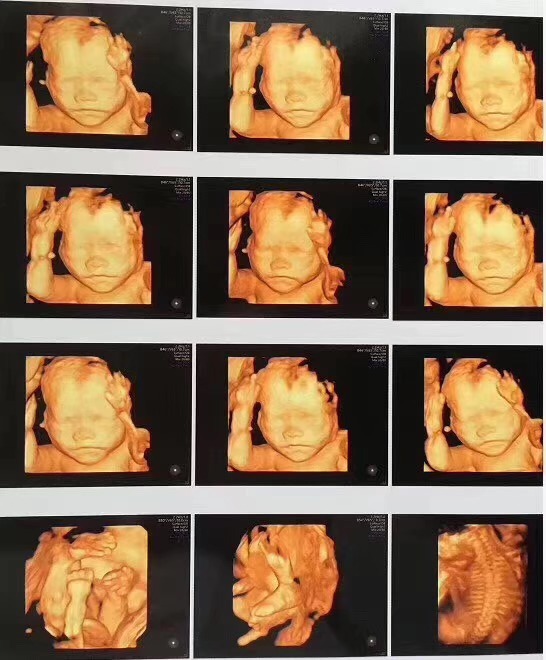

四维彩超的全称是四维彩色超声诊断仪,四维彩超能够表面成像,可以更加清晰的查看胎儿是否存在先天性体表畸形,如脑膜膨出、唇腭裂、脊柱裂等先天畸形,及早发现及早做出解决方案。

佛山都市妇产医院妇产科陆耀宁主任表示:因为这个时期正是大脑突飞猛进的发育时期,这个时期的胎儿结构已经形成,胎儿的大小以及羊水适中,在宫内的活动空间较大,胎儿骨骼回声影响比较小,图像也比较清晰。

选择在这个时间范围里做检查,除了能更好地排畸以外,还能看到宝宝生长的样子。

佛山都市妇产医院引进美国GE四维彩超,画面更清晰,排畸更准确,能够全方位、多角度检查胎儿的生长发育情况,孕妈妈可以通过四维彩超与宝宝提前见面,感受生命最初的感动。